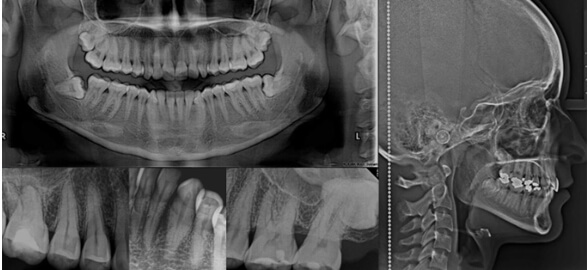

En la práctica odontológica moderna, la radiografía dental se ha convertido en una herramienta indispensable.